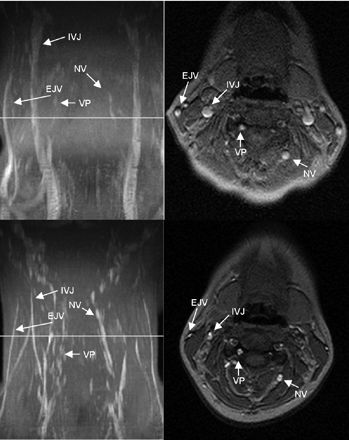

Table 1 shows the delineation of the IJV and collateral vessels in both positions. A great variability of the cerebral blood outflow tract was noted (Figs 1⇓⇓–4). In the supine position, additional vessels besides the IJV contributing to the cerebral venous outflow could be identified in all volunteers (Figs 1⇓⇓–4). The EJV was visible in 13 volunteers; the VP, in 5 volunteers; and the NV, in 7 volunteers.

MIP (left column) and axial source images at the level of C4 in the supine (top row) and sitting positions (bottom row) in a healthy volunteer. In the supine position, there is no significant narrowing of the IJV. The EJV, NV, and the VP can be identified in the supine position. In the sitting position, the IJV, EJV, and the NV are much less prominent, whereas the VP is slightly more prominent.